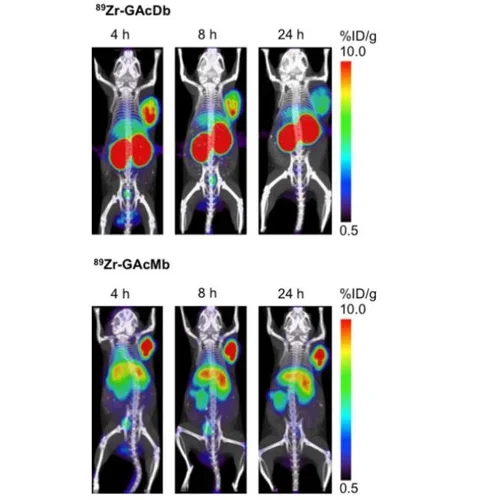

Breadcrumb Home Applications Gallery Gallery Applications Videos Gallery Library of Recent Studies Cancer Biology Coupling IL-2 with IL-10 to mitigate toxicity and enhance antitumor immunity. Ahn et al. 2025. Cell Rep Med. PGC-1α drives small cell neuroendocrine cancer progression toward an ASCL1-expressing subtype with increased mitochondrial capacity. Varuzhanyan et al. 2024. Proc Natl Acad Sci U S A. 89Zr-ImmunoPET for the Specific Detection of EMP2-Positive Tumors. Chan et al. 2024. Mol Cancer Ther. 18F-Labeled brain-penetrant EGFR tyrosine kinase inhibitors for PET imaging of glioblastoma. Narayanam et al. 2023. Chem Sci. M2 isoform of pyruvate kinase rewires glucose metabolism during radiation therapy to promote an antioxidant response and glioblastoma radioresistance. Bailleul et al. 2023. Neuro Oncol. Spatial mapping of mitochondrial networks and bioenergetics in lung cancer. Han et al. 2023. Nature. Anti-PD-1/L1 lead-in before MAPK inhibitor combination maximizes antitumor immunity and efficacy. Wang et al. 2021. Cancer Cell. In vivo imaging of mitochondrial membrane potential in non-small-cell lung cancer. Momcilovic et al. 2019. Nature. Immunotherapy Low-dose exposure to PBDE disrupts genomic integrity and innate immunity in mammary tissue. Lamkin et al. 2022. Front Genet. Immuno-PET in Inflammatory Bowel Disease: Imaging CD4-Positive T Cells in a Murine Model of Colitis. Freise et al. 2018. J Nucl Med. ImmunoPET of Malignant and Normal B Cells with 89Zr- and 124I-Labeled Obinutuzumab Antibody Fragments Reveals Differential CD20 Internalization In Vivo. Zettlitz et al. 2017. Clin Cancer Res. Detection of immune responses after immunotherapy in glioblastoma using PET and MRI. Antonios et al. 2017. Proc Natl Acad Sci U S A. Neuroscience [18F]FDG-PET and [18F]MPPF-PET are brain biomarkers for the creatine transporter Slc6a8 loss of function mutation. Day et al. 2025. Sci Rep. Gene therapy for guanidinoacetate methyltransferase deficiency restores cerebral and myocardial creatine while resolving behavioral abnormalities. Khoja et al. 2022. Mol Ther Methods Clin Dev. Regional distribution of SGLT activity in rat brain in vivo. Yu et al. 2013. Am J Physiol Cell Physiol. [F-18]FDDNP microPET imaging correlates with brain Aβ burden in a transgenic rat model of Alzheimer disease: effects of aging, in vivo blockade, and anti-Aβ antibody treatment. Teng et al. 2011. Neurobiol Dis. Cardiology Preclinical evaluation of high-resolution CT, 18F-FDG, and 18F-NaF PET imaging for longitudinal monitoring of atherosclerosis. Tamboline et al. 2025. Eur J Nucl Med Mol Imaging. A humanized monoclonal antibody targeting an ectonucleotidase rescues cardiac metabolism and heart function after myocardial infarction. Li et al. 2024. Cell Rep Med. Invasive electrochemical impedance spectroscopy with phase delay for experimental atherosclerosis phenotyping. Chen et al. 2024. FASEB J. Changes in microarchitecture of atherosclerotic calcification assessed by 18F-NaF PET and CT after a progressive exercise regimen in hyperlipidemic mice. Hsu et al. 2021. J Nucl Cardiol. Statin Effects on Vascular Calcification: Microarchitectural Changes in Aortic Calcium Deposits in Aged Hyperlipidemic Mice. Xian et al. 2021. Arterioscler Thromb Vasc Biol. Statin Effects on Vascular Calcification: Microarchitectural Changes in Aortic Calcium Deposits in Aged Hyperlipidemic Mice. Xian et al. 2021. Arterioscler Thromb Vasc Biol. Effects of teriparatide on morphology of aortic calcification in aged hyperlipidemic mice. Hsu et al. 2018. Am J Physiol Heart Circ Physiol. Metabolism PPARγ-dependent remodeling of translational machinery in adipose progenitors is impaired in obesity. Siqueira et al. 2024. Cell Rep. Dietary control of peripheral adipose storage capacity through membrane lipid remodelling. Tol et al. 2025. Nat Metab. Drug Development Recent developments in translational imaging of in vivo gene therapy outcomes. Day et al. 2025. Mol Ther. A Glucose-Responsive Glucagon-Micelle for the Prevention of Hypoglycemia. Vinciguerra et al. 2024. ACS Cent Sci. A humanized monoclonal antibody targeting an ectonucleotidase rescues cardiac metabolism and heart function after myocardial infarction. Li et al. 2024. Cell Rep Med. An HK2 Antisense Oligonucleotide Induces Synthetic Lethality in HK1-HK2+ Multiple Myeloma. Xu et al. 2019. Cancer Res. A precision therapeutic strategy for hexokinase 1-null, hexokinase 2-positive cancers. Xu et al. 2018. Cancer Metab. Development of new deoxycytidine kinase inhibitors and noninvasive in vivo evaluation using positron emission tomography. Murphy et al. 2013. J Med Chem. On-demand drug release system for in vivo cancer treatment through self-assembled magnetic nanoparticles. Lee et al. 2013. Angew Chem Int Ed Engl. Accurate Measurements by High-Resolution CT and MRI Supramolecular hydrogel actuators with reprogrammable magnetic orientation by locally mediated viscoelasticity and pinning force. Zhang et al. 2025. Sci Adv. Gene therapy for guanidinoacetate methyltransferase deficiency restores cerebral and myocardial creatine while resolving behavioral abnormalities. Khoja et al. 2022. Mol Ther Methods Clin Dev. Interactions between maternal fluoxetine exposure, the maternal gut microbiome and fetal neurodevelopment in mice. Vuong et al. 2021. Behav Brain Res. Imaging Technology Development Real-Time in Vivo Bacterial Imaging by Computed Tomography and Fluorescence Using Phage-Gold Nanorod Bioconjugates as Contrast Agents. Peng et al. 2025. ACS Biomater Sci Eng. Retrospective Cardiac Gating with A Prototype Small-Animal X-ray Computed Tomograph. Taschereau et al. 2025. J Vis Exp. Novel Quantification Protocol for Cardiovascular Calcification Progression Using Longitudinal MicroPET/MicroCT Images. Day et al. 2024. J Vis Exp. High-throughput radio-TLC analysis. Wang et al. 2021. Nucl Med Biol. Performance evaluation of HiPET, a high sensitivity and high resolution preclinical PET tomograph. Gu et al. 2020. Phys Med Biol. Prediction of major torso organs in low-contrast micro-CT images of mice using a two-stage deeply supervised fully convolutional network. Wang et al. 2019. Phys Med Biol. Performance Evaluation of G8, a High-Sensitivity Benchtop Preclinical PET/CT Tomograph. Gu et al. 2019. J Nucl Med. 3D Printing for Understanding Anatomy Three-Dimensional Magnetic Resonance Imaging of the Human Stellate Ganglion. Nakajo et al. 2025. Clin Anat. Understanding Cardiac Anatomy and Imaging to Improve Safety of Procedures: The Subclavian Artery and Vein. Sato et al. 2025. JACC Case Rep. Understanding Cardiac Anatomy and Imaging to Improve Safety of Procedures: The Femoral Artery and Vein: Part 2. Sato et al. 2024. JACC Case Rep. Pipeline for Multi-Scale Three-Dimensional Anatomic Study of the Human Heart. Hanna et al. 2024. J Vis Exp. Radiochemistry Technology Development Rapid Concentration of Ga-68 and Proof-of-Concept Microscale Labeling of [68Ga]Ga-PSMA-11 in a Droplet Reactor. Lu et al. 2024. Molecules. Scalable droplet-based radiosynthesis of [18F]fluorobenzyltriphenylphosphonium cation ([18F]FBnTP) via a "numbering up" approach. Lu et al. 2024. Lab Chip. Proof-of-concept optimization of a copper-mediated 18F-radiosynthesis of a novel MAGL PET tracer on a high-throughput microdroplet platform and its macroscale translation. Lu et al. 2023. Lab Chip. Accelerating radiochemistry development: Automated robotic platform for performing up to 64 droplet radiochemical reactions in a morning. Jones et al. 2023. Chem Eng J. Detrimental impact of aqueous mobile phases on 18F-labelled radiopharmaceutical analysis via radio-TLC. Laferriere-Holloway et al. 2023. Anal Methods. High-pressure, compact, modular radiosynthesizer for production of positron emitting biomarkers. Amaraesekera et al. 2013. Appl Radiat Isot. Simplified programming and control of automated radiosynthesizers through unit operations. Clagget et al. 2013. EJNMMI Res. High-Efficiency Production of Radiopharmaceuticals via Droplet Radiochemistry: A Review of Recent Progress. Wang et al. 2020. Mol Imaging. A simple and efficient automated microvolume radiosynthesis of [18F]Florbetaben. Lisova et al. 2020. EJNMMI Radiopharm Chem. Probe and Assay Development Comparison of the Efficacy and Sensitivity of Alternative PET Reporter Gene/PET Reporter Probe Systems That Minimize Biological Variables. Xu et al. 2020. Methods Mol Biol. A Transmetalation Reaction Enables the Synthesis of [18F]5-Fluorouracil from [18F]Fluoride for Human PET Imaging. Hoover et al. 2016. Organometallics. INDs for PET molecular imaging probes-approach by an academic institution. Mosessian et al. 2014. Mol Imaging Bio. Positron emission tomography probe demonstrates a striking concentration of ribose salvage in the liver. Clark et al. 2014. Proc Natl Acad Sci U S A. Tracer Kinetic Modeling Improved modeling of in vivo kinetics of slowly diffusing radiotracers for tumor imaging. Wilks et al. 2014. J Nucl. Med. Improved derivation of input function in dynamic mouse [18F]FDG PET using bladder radioactivity kinetics. Wong et al. 2013. Mol Imaging Biol. Influence of dietary state and insulin on myocardial, skeletal muscle and brain [F]-fluorodeoxyglucose kinetics in mice. Effects of administration route, dietary condition, and blood glucose level on kinetics and uptake of 18F-FDG in mice. Wong et al. 2011. J Nucl Med.